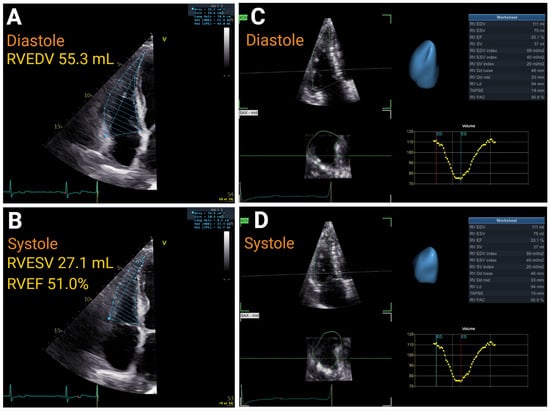

| 3D RVEF, % | >45 | ≤45 to <39 | ≤39 to ≤32 | <32 | r = 0.56 to 0.95 | |